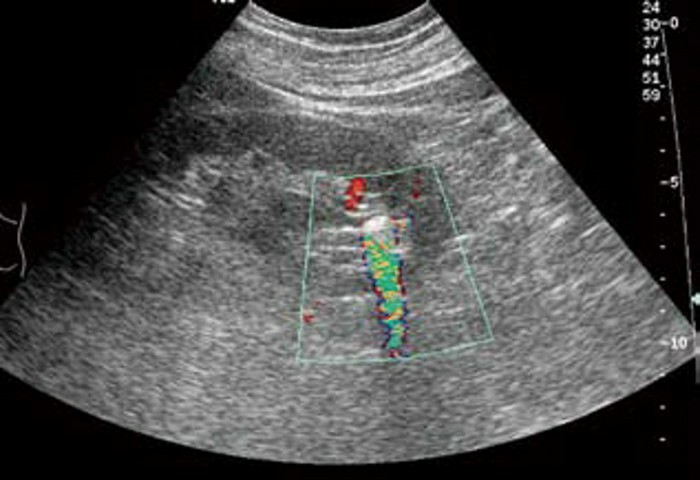

1. 肾内小结石:一般出现在肾乳头旁,表现为圆形或椭圆形的强回声斑点,周围有少量无回声区,后方可有淡声影,有的则不明显。CDFI 显示“闪烁”伪像,有助于小结石的识别。